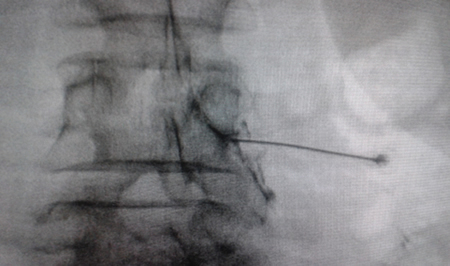

Figura 1